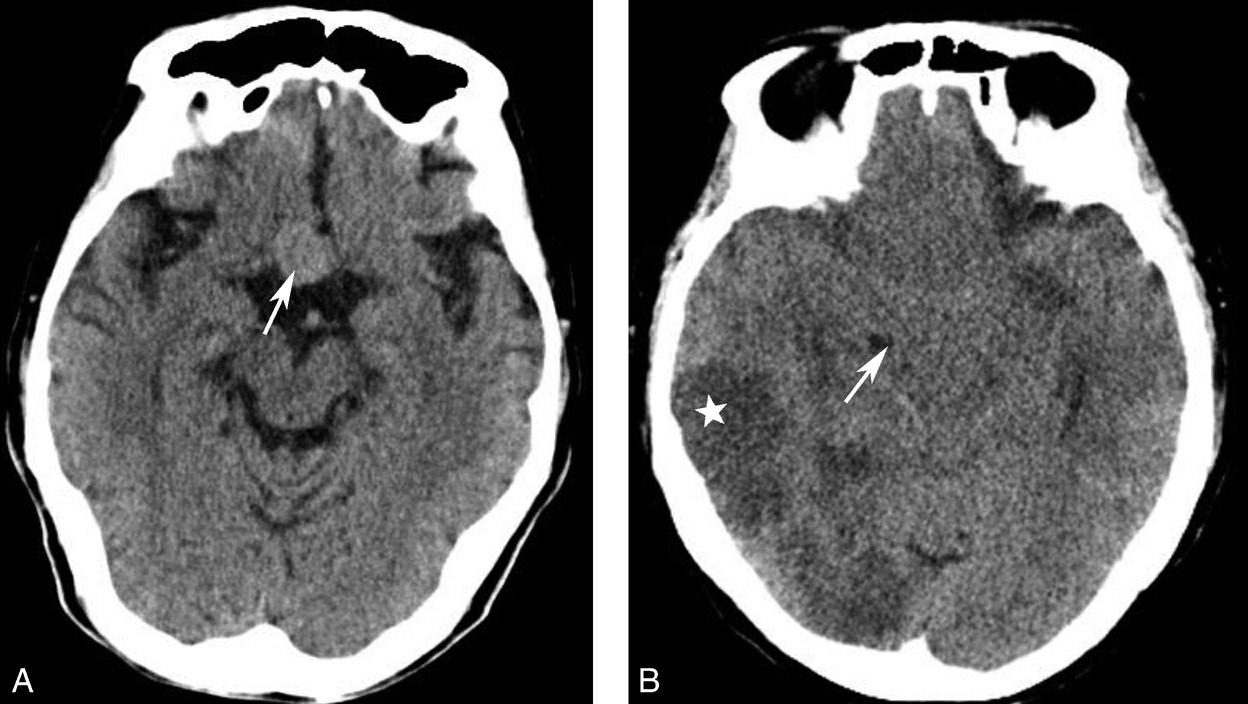

图1-2-18 鞍上池形态改变

A.鞍上池前角消失,失去正常六角星形态;此例为垂体腺瘤向鞍上生长,占据此区域所致(箭);B.鞍上池闭塞;此病例为双侧大脑半球多发大面积梗死(☆),弥漫性脑肿胀,导致鞍上池闭塞(箭)

图1-2-20 环池闭塞

右侧颞叶脑内大血肿(★),产生严重的占位效应,环池受压闭塞(箭),脑疝形成